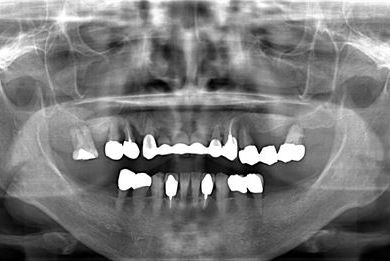

インプラントの症例写真 IMPLANT

| 性別/年齢 | 女性 / 58歳 | ||||||||||||||||||||||||||||||||

| 主訴 | インプラント治療を希望。 | ||||||||||||||||||||||||||||||||

| 治療内容 | インプラント8本(抜歯即日スピードインプラント、サイナスリフト)、ハイブリッドセラミック8本 | ||||||||||||||||||||||||||||||||

| 総治療費 | 3,495,050円 | ||||||||||||||||||||||||||||||||

| 治療期間 | 1年0ヶ月 |